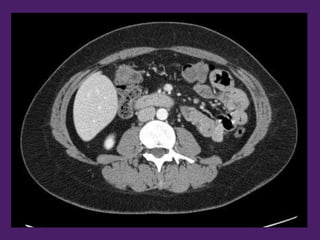

Aorta

2da porción

del duodeno

Riñón

izquierdo

Lóbulo

derecho

del hígado

Vena

cava

inferior

3ra porción

Vena mesentérica

superior

Colon

transverso

descendente

Asas

yeyunoileales

Hígado